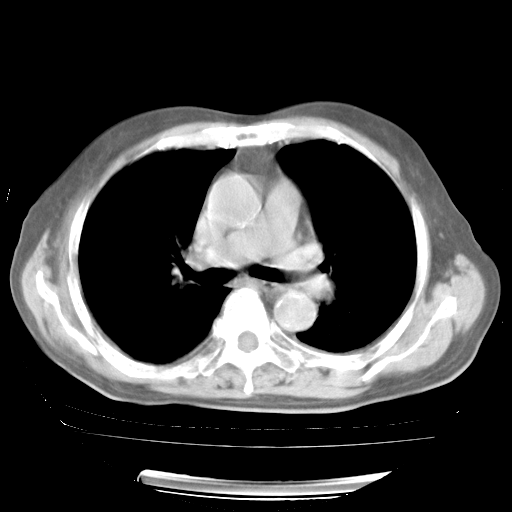

4月28日肺部CT